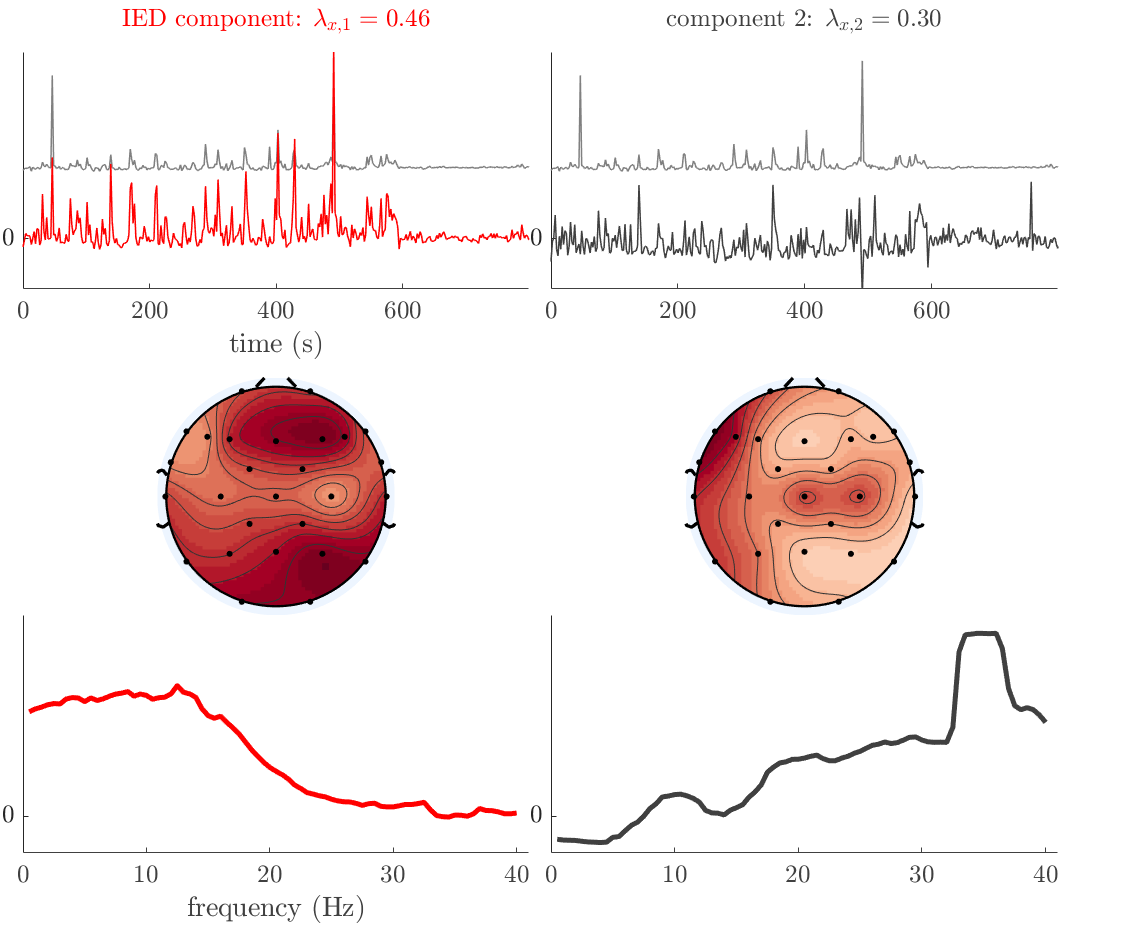

Patient 1

We analyze the solution with sources. Figure 1 shows the EEG signatures and HRF waveforms. One of the sources is highly correlated to the MWF reference (in grey), which was already known from Table B.3. This IED-related source had a typical low-frequency spectrum, which is expected for the typical spike-and-wave interictal discharges. The topography is relatively diffuse, although the highest amplitudes are mostly in the left hemisphere. This is in accordance with the lateralization of ictal onset zone (left temporal lobe, cfr. Table 1). There are some noteworthy observations to be made about some of the other components. The fourth has an unusually sharp spectrum, is mainly localized on two nonadjacent center electrodes, and is sustained for a single period of many seconds Hence, this component likely captured an artifact (of yet unknown origin), although we spotted no large-amplitude changes in the EEG itself. Similarly, the third source is only present at one frontal electrode, and exists in a frequency range above 20 Hz. It might represent a muscle artifact, e.g., due to frowning or twitching of some muscles in the forehead. The HRFs of all ROIs are shown in Figure 1(b). Two of the basis functions seem to have converged to a very similar waveform, which is an unfortunate possibility if two initial HRFs are too close to the same local optimum in their respective parameters. This reduces the expressive power of the basis set, which is clearly visible, since many ROIs have a nearly identical HRF. One of the twenty ROIs with the highest-entropy HRF overlapped the IOZ, although clearly this HRF (bold line) is not among the most dissimilar waveforms for this patient. This is also visible in Figure 2: both the HRF entropy and extremity maps show a small overlap with the delineated IOZ. Despite the good correspondence in the EEG domain, no significant (de)activation of the IED-component is found inside the IOZ.